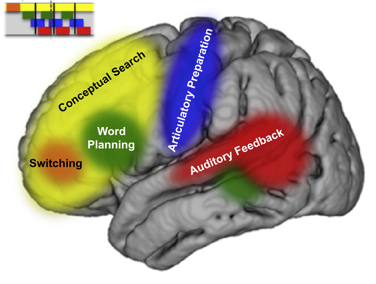

Neurophysiology of consciousness and cognition

Dr. Williams Roberson’s team studies the brain activity patterns underlying consciousness and cognitive functions such as language production, perception and memory, and seeks to use these patterns to optimize the care of patients with central nervous system disorders such as delirium, dementia, epilepsy, and stroke. We use computational and quantitative analysis techniques to investigate the neurophysiological basis of cognitive functions in health and in neurologically impaired states. We are currently conducting an observational study developing quantitative EEG-based biomarkers of ICU delirium, post-ICU cognitive impairment and post-ICU psychological distress. We will use these biomarkers to identify patients most at risk for symptoms of post-intensive care syndrome (PICS), and subsequently to develop and validate targeted neuromodulatory interventions to improve cognitive and psychological outcomes in survivors of critical illness.